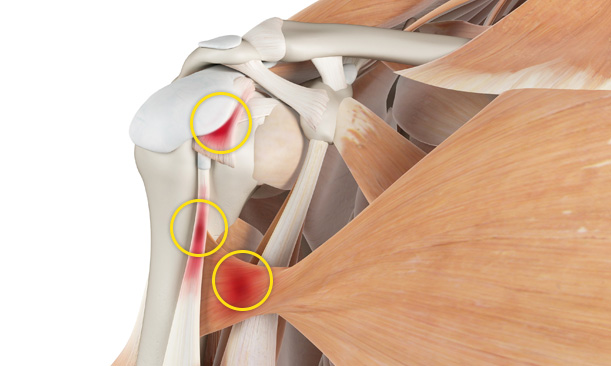

어깨충돌증후군이 발생하게 되면 회전근개에 염증이 발생하게 되고

급성 부종을 일으키게 됩니다.

관절 내시경을 통한

견봉 성형술

관절 내시경을 통하여

힘줄 손상을 유발하는 견봉하 골극을 제거합니다.